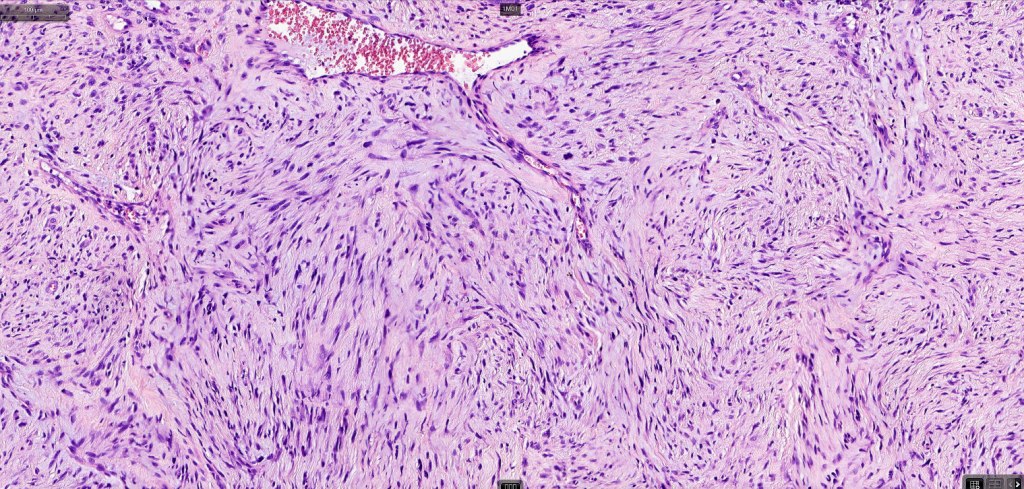

•Paucicellular spindle cell infiltrate with “myxoid” fine to a dense collagenous stroma

•Hyperchromatic nuclei

•Variable pleomorphism